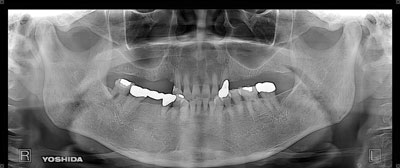

症例1

治療前

治療後

主訴 左上小臼歯から大臼歯部にかけて、脱離・歯冠崩壊、及び欠損があり、左奥では物が噛めない。

まだ年齢も50代と若く、義歯は煩わしく嫌であるという訴えがあり、左上5番・6番にインプラントを2本埋入する計画を立案。

副鼻腔までの距離がわずかしかないので、ソケットリフトと、骨の緻密化を計る為に、C・C・Wドリリング法を併用。

オぺから仮歯装着まで3ヶ月を要し、4ヶ月未満の治療期間を経て最終補綴物ジルコニア2本を装着。

リスクとしては、ソケットリフト(骨造成)による一過性の副鼻腔炎が起きる可能性がある。まれに洞底膜が破れる可能性がある。

ただし、膜は約3週で再生するので、膜の回復を待ち、再オペを行う。

費用 116万(オペ・ソケットリフト・人工骨・採血による濃縮血小板生成・仮歯・最終補綴物まで含む)